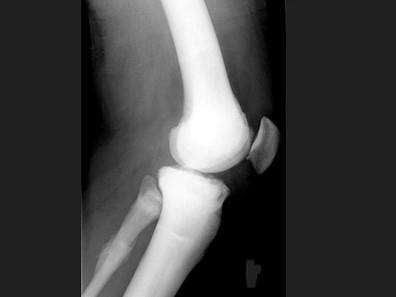

男,21岁,曾多次有过骨折史,结合图像,最可能的诊断是?(?)A.石骨症B.成骨不全C.畸形性骨炎D.转移性骨肿瘤E.氟骨症

问题 男,21岁,曾多次有过骨折史,结合图像,最可能的诊断是?(?)

选项 A.石骨症 B.成骨不全 C.畸形性骨炎 D.转移性骨肿瘤 E.氟骨症

答案 A